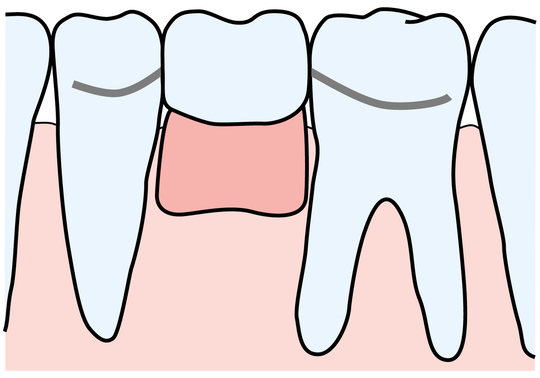

ブリッジ

人間の歯はサメのように何度も生え変わりをすることはありません。つまり永久歯は一度抜けると二度と生えてきません。抜歯後には、ブリッジ・入れ歯・インプラントという方法がとられるのが一般的です。どの方法も一長一短ですが、すべてに共通するのが『抜歯が前提であり、歯根膜が失われた状態での修復である』ということです。

親知らずを抜歯箇所に移植するのは、他の3つの方法に比べて制限はあるものの、歯根膜を得ることができるということで大きな意味があります。また、前後の歯を削ったり、負荷をかけるブリッジや入れ歯に代わる方法として保険が利くのも魅力です。(保険がきかない場合もあります)予後が読みにくく、多少不確定要素もありますが、上記3つの方法加えて、第4の方法となります。